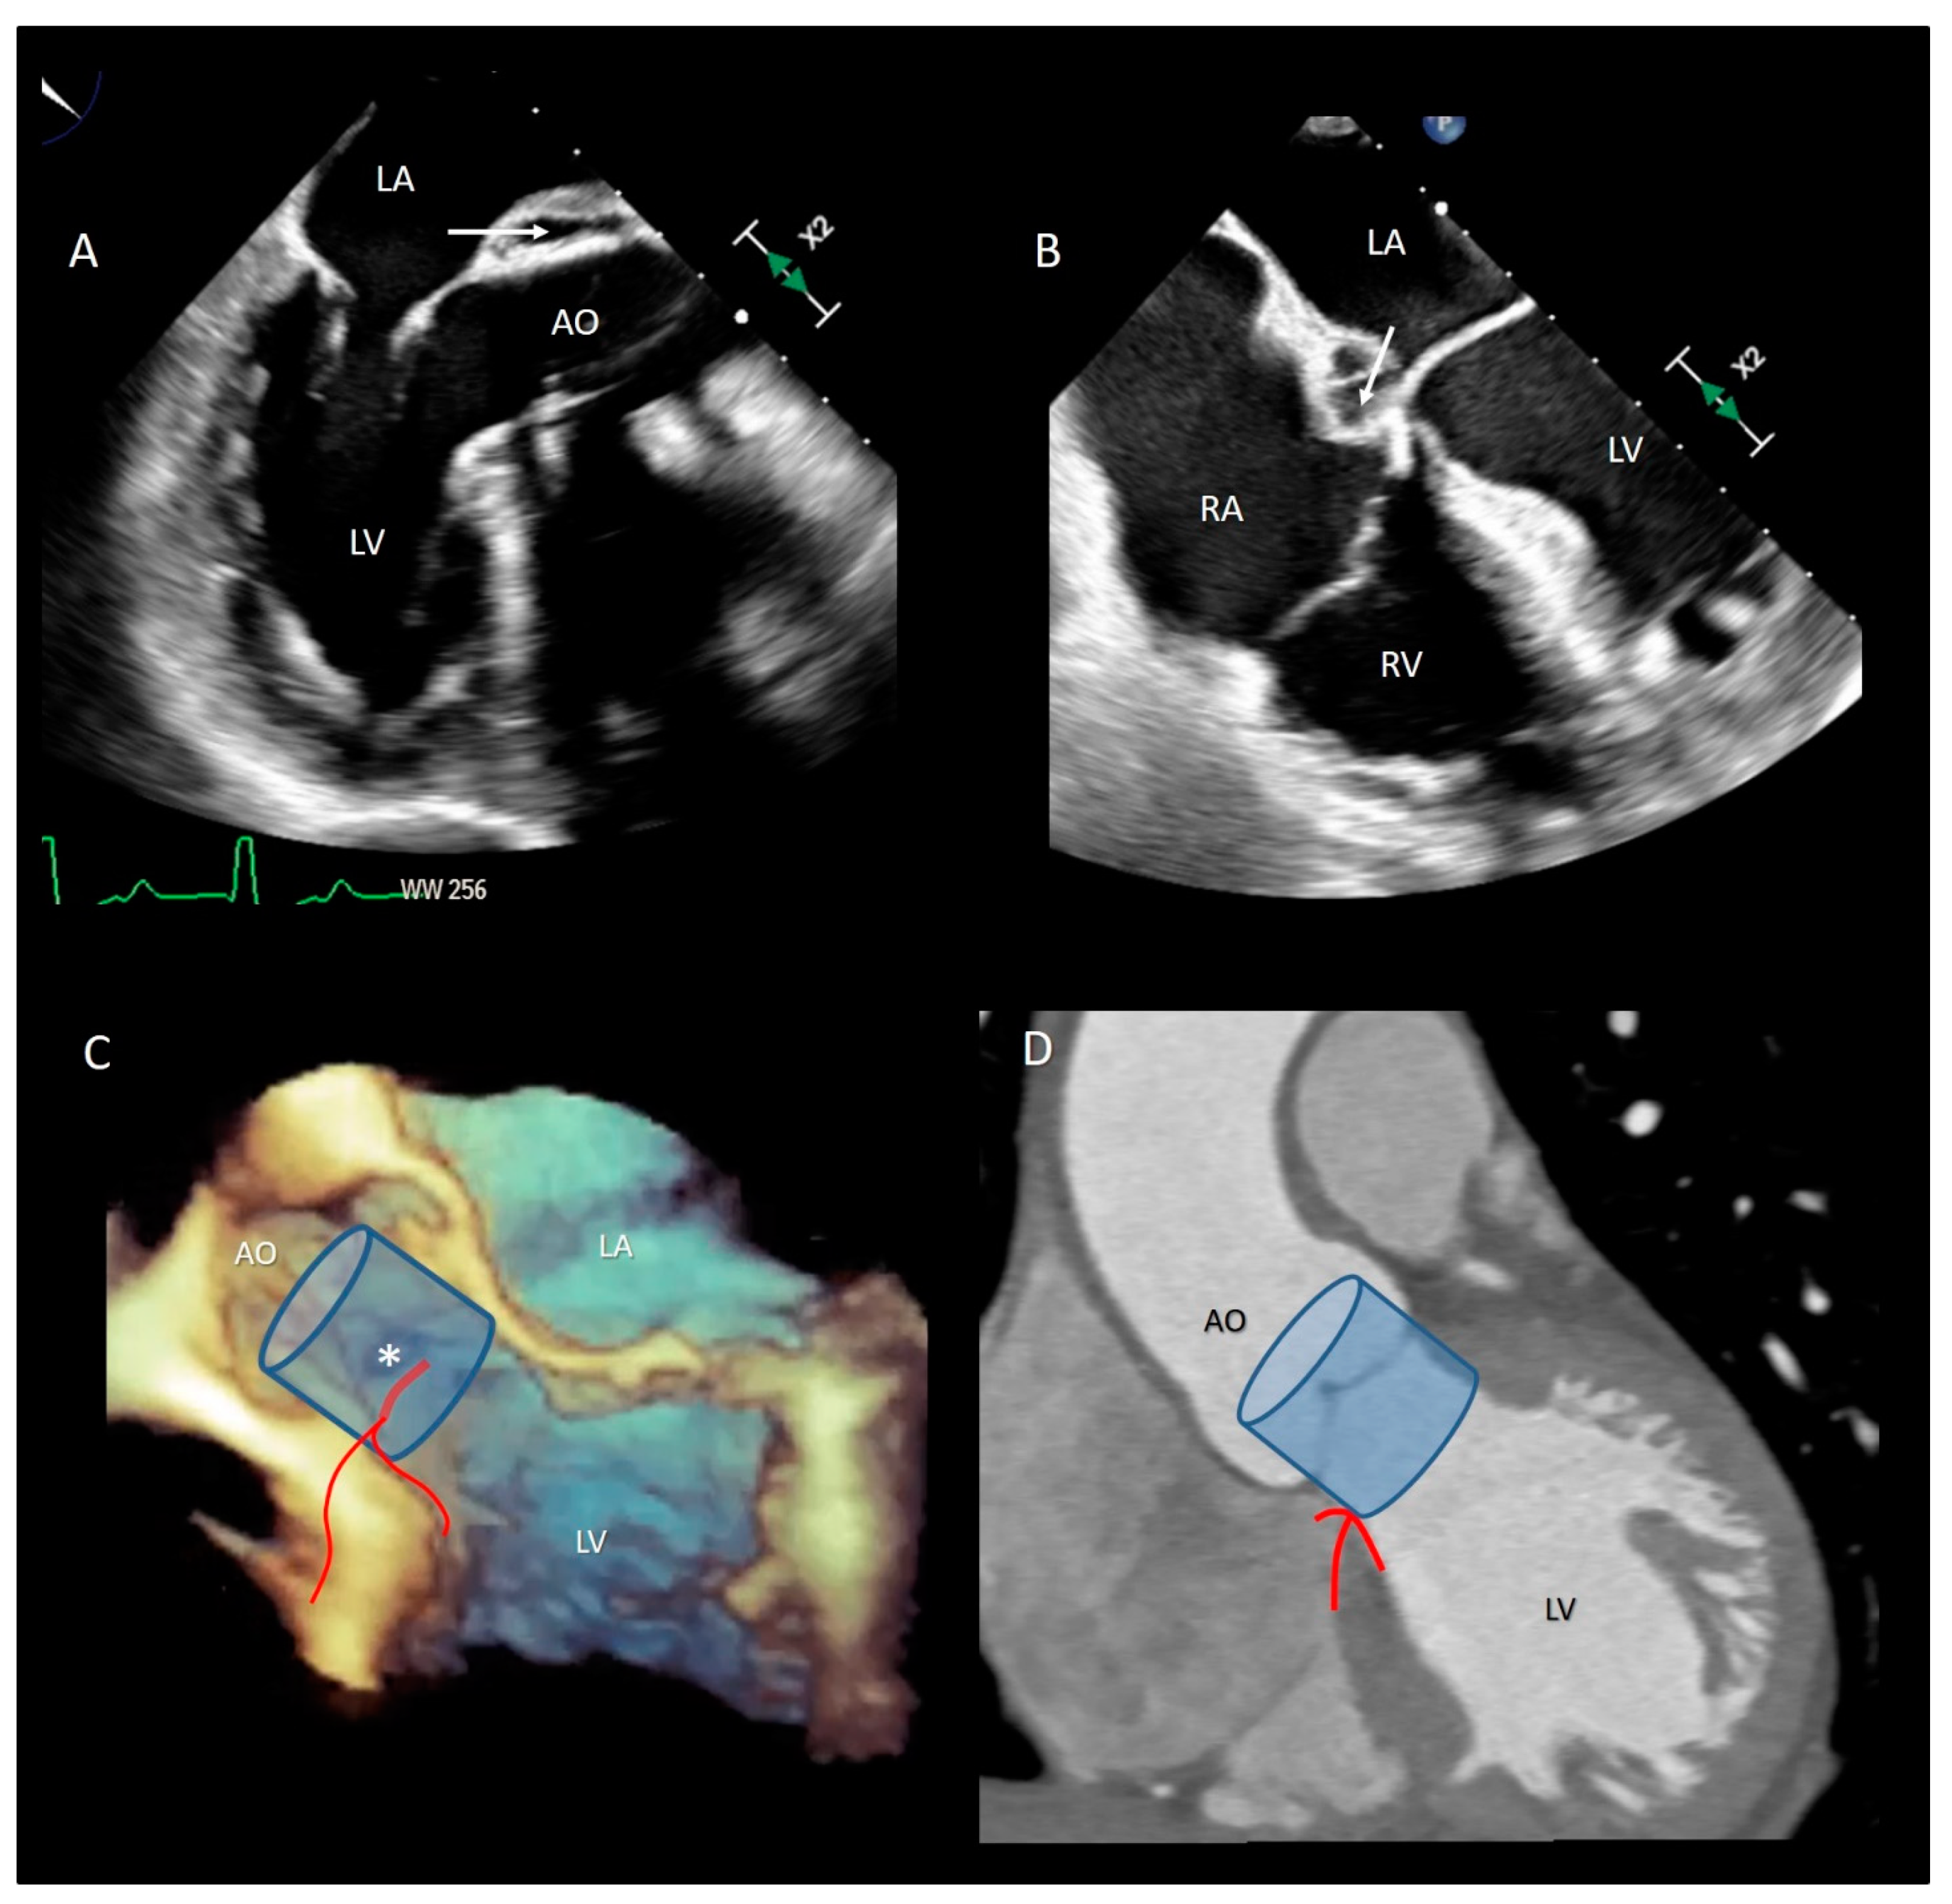

3.3.2. The Muscular Component of VAJ

3.4. The Fibrous Component of VAJ